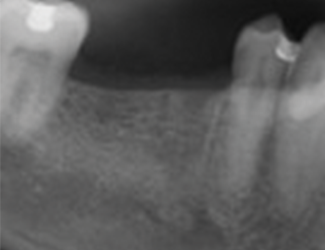

Implantatbehandling utfördes med Straumann TLX SLActive 4,5 x 10 mm RT i region 45 samt Straumann TLC SLActive 4,5 x 10 mm RT i region 46. Implantaten installerades med ett insättningsmoment på 45 Ncm. Vid initial ISQ-mätning uppvisade båda implantaten ett värde på 79, vilket indikerade god primär stabilitet. Efter åtta veckors läkning bedömdes implantaten som stabila för avtryckstagning inför permanent protetisk rehabilitering, med ett uppmätt ISQ-värde på 88.

1. Utgångsläge före implantatinstallation.

2. Implantatinstallation region 45 & 46.